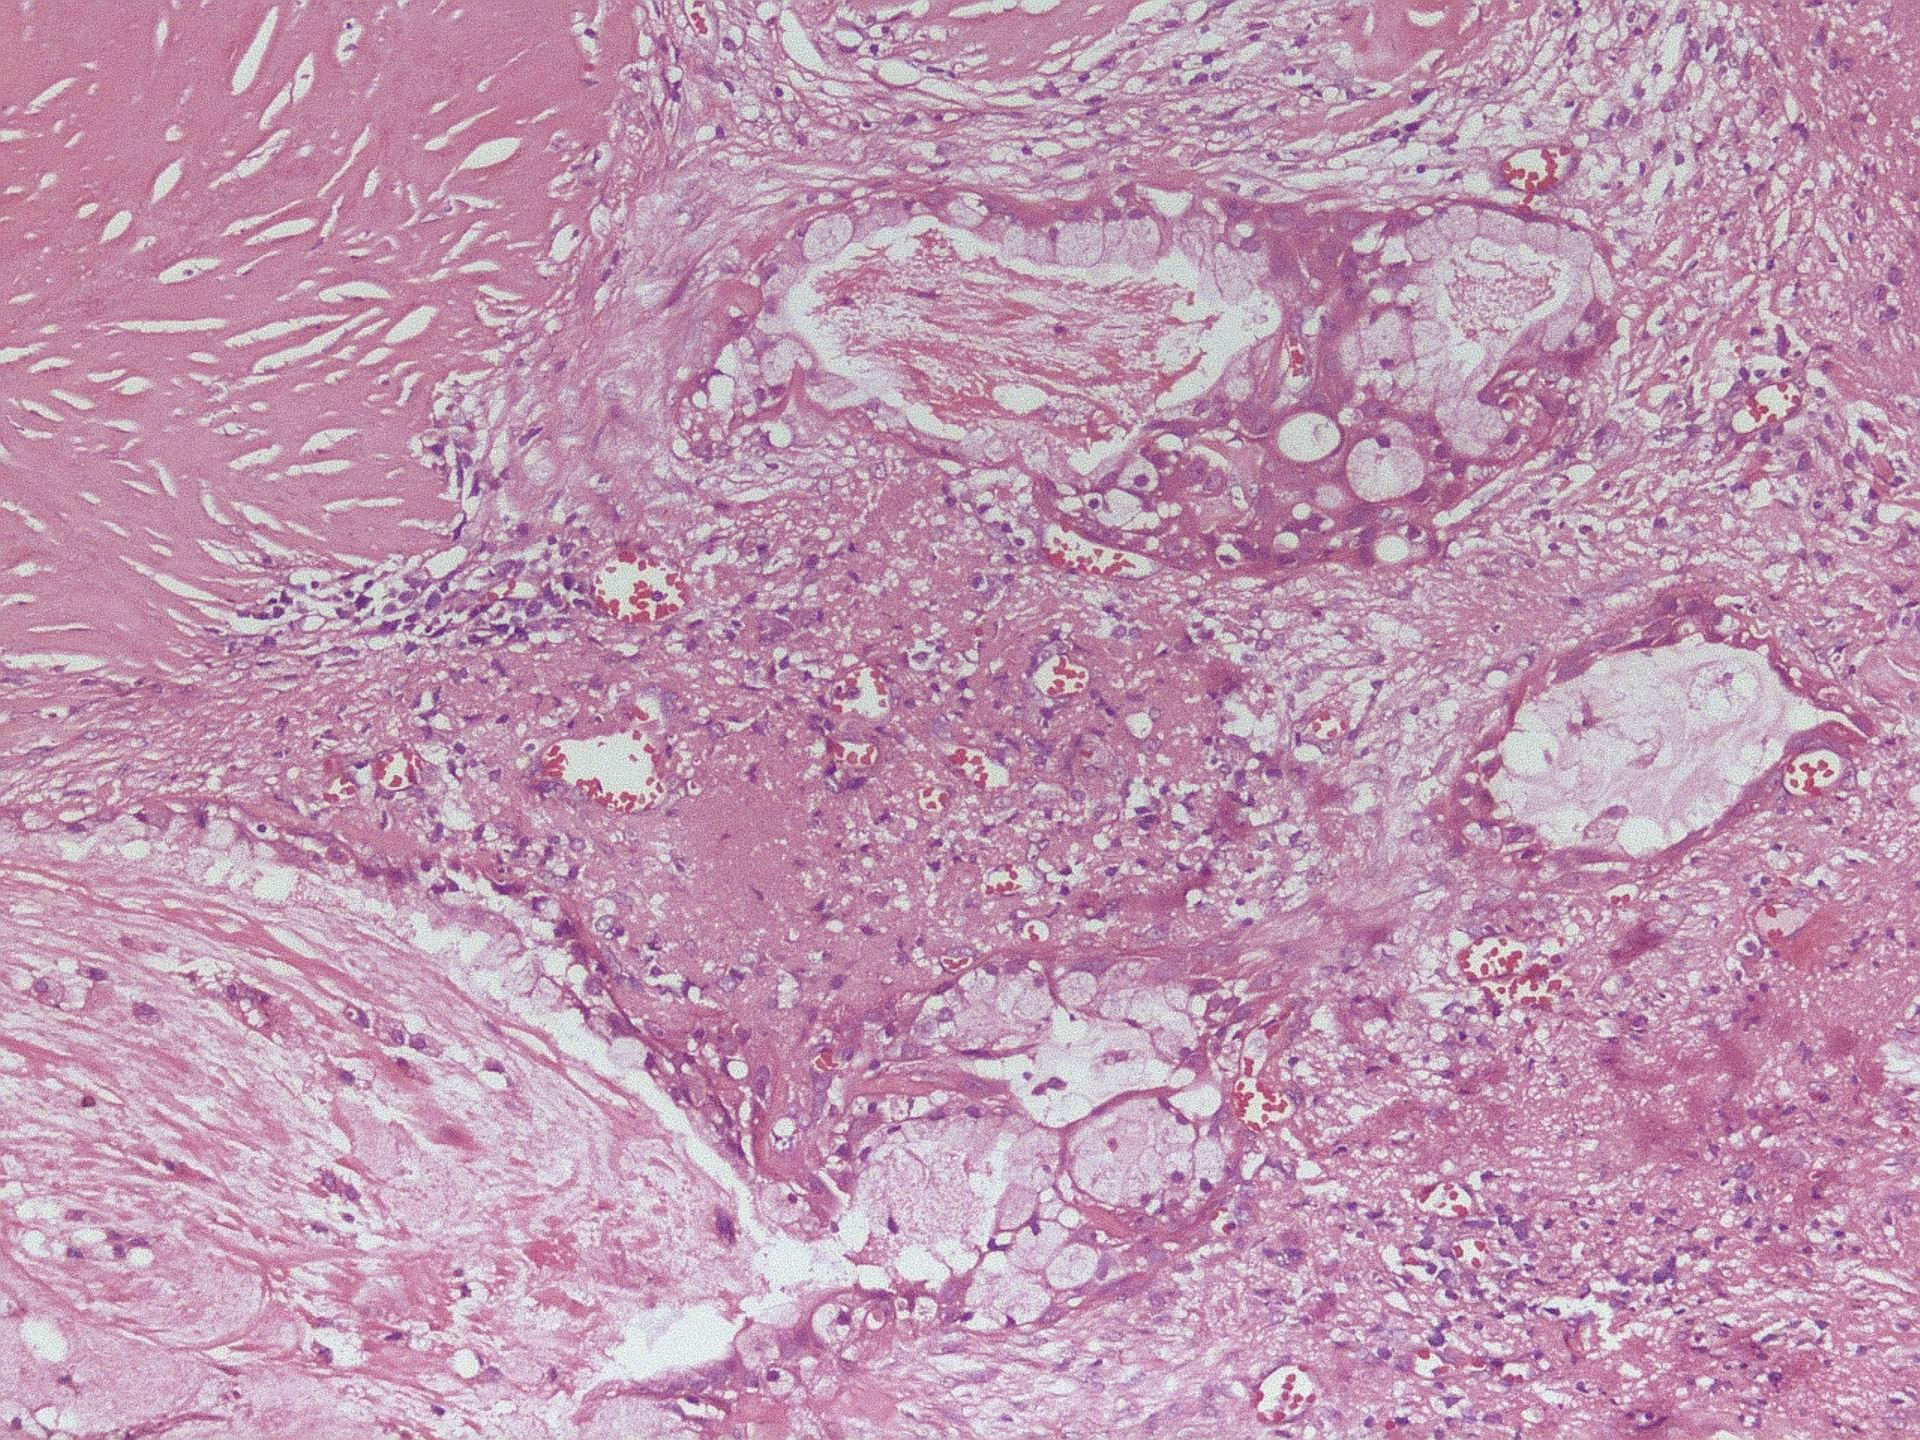

3、镜检

粘表皮样癌由粘液细胞、表皮样细胞及中间细胞组成。粘液样细胞成熟时呈杯状或柱状,细胞基部有明显的胞质和细胞核;未成熟时呈腺癌细胞样,胞浆有粘液,染色为胭脂红。类似于口腔粘膜的鳞状上皮,表皮样细胞有间桥,偶尔出现角化。

其体积较小,胞浆较少,呈立方体状,类似于上皮的基底细胞。中间体可以分化为粘液细胞和表皮样细胞。在分化良好的病人中,有大量的粘液样细胞和表皮样细胞,少数为中间细胞。肿块可以形成不规则的鳞片,但通常形成大小不一的囊肿。在囊肿内膜常可见粘液细胞。粘细胞可包覆于表皮样细胞或混合于表皮样细胞中。更大的囊肿可能有突出物和红色粘液。低分化者主要为表皮样细胞和中间细胞,粘液样细胞较少。其细胞间变性明显,有丝分裂,上皮实质增多,囊腔减少,肿瘤浸润周围组织较少。